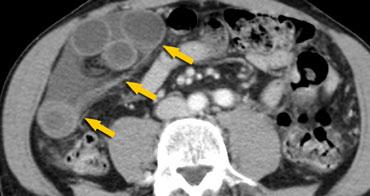

Bên trái là hình ảnh điển hình của xoắn manh tràng.

Chúng ta có thể thấy vùng chuyển tiếp hình mỏ chim nằm ở góc phần tư dưới bên phải, cho thấy đây là xoắn manh tràng.

Manh tràng giãn nằm ở góc phần tư trên bên trái.

Cũng lưu ý đại tràng xuống xẹp nằm phía sau manh tràng giãn (mũi tên cong).